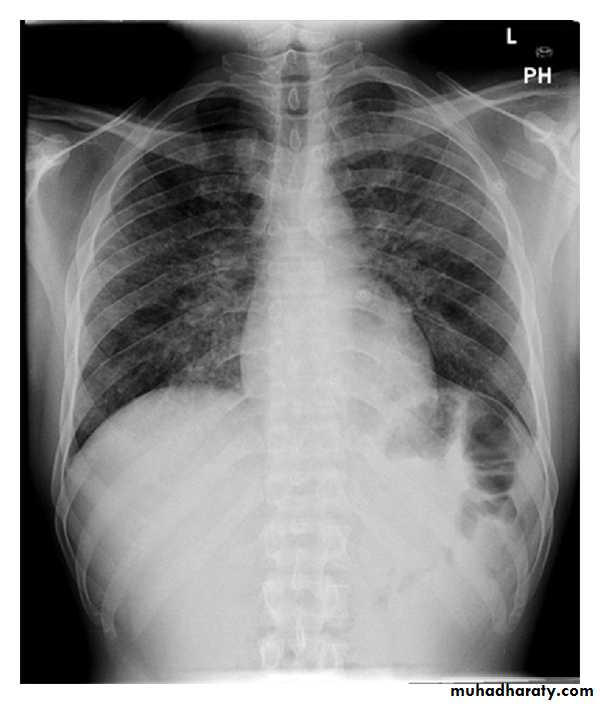

- Bilateral hilar lymphadenopathy , asymptomatic, subside without treatment in about 80-90% of patients

- Pulmonary infiltration and bilateral hilar lymphadenopathy which may cause symptoms such as dyspnoea, cough and fever, but subsides in 40% of patients

- Pulmonary fibrosis with diffuse infiltration, ultimately leading to a restrictive defect on respiratory function testing.

Pulmonary infeltrate

Hilar adenopathy